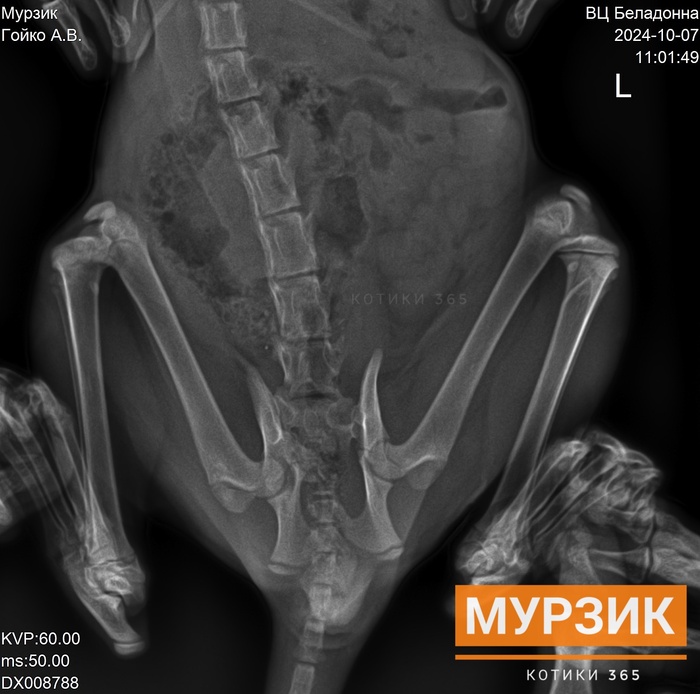

Помимо перелома таза, трещины в большеберцовой кости, отрыва хвоста и лапы, у Мурзика обнаружили ещё глубокую опоясывающую рваную рану хвоста. До кости.

Удастся ли сохранить кончик хвоста, пока не ясно. Чувствительности в хвосте, из-за отрыва, нет. Главное, чтобы не было нагноения.

На предоперационной подготовке Мурзика ещё раз внимательно осмотрели, прощупали, протрогали, посмотрели как он ходит, проверили какая чувствительность у задних лап. Сделали дополнительные рентгеновские снимки в разных проекциях. Смотрели, думали. И пришли к выводу, что на сегодняшний день, в срочной операции нет необходимости.

"Выявлен перелом лонной, седалищной костей слева и отрыв подвздошно-крестцового сочленения слева, отрыв хвостовых позвонков и трещина большеберцовой кости слева".

Рекомендовано вольерное содержание 1 месяц.

Чувствительность в задних лапах есть. Мурзик на них опирается, ходит. Ему не больше трёх месяцев, он маленький и лёгкий - на суставы нагрузка не большая. Всё должно срастись.